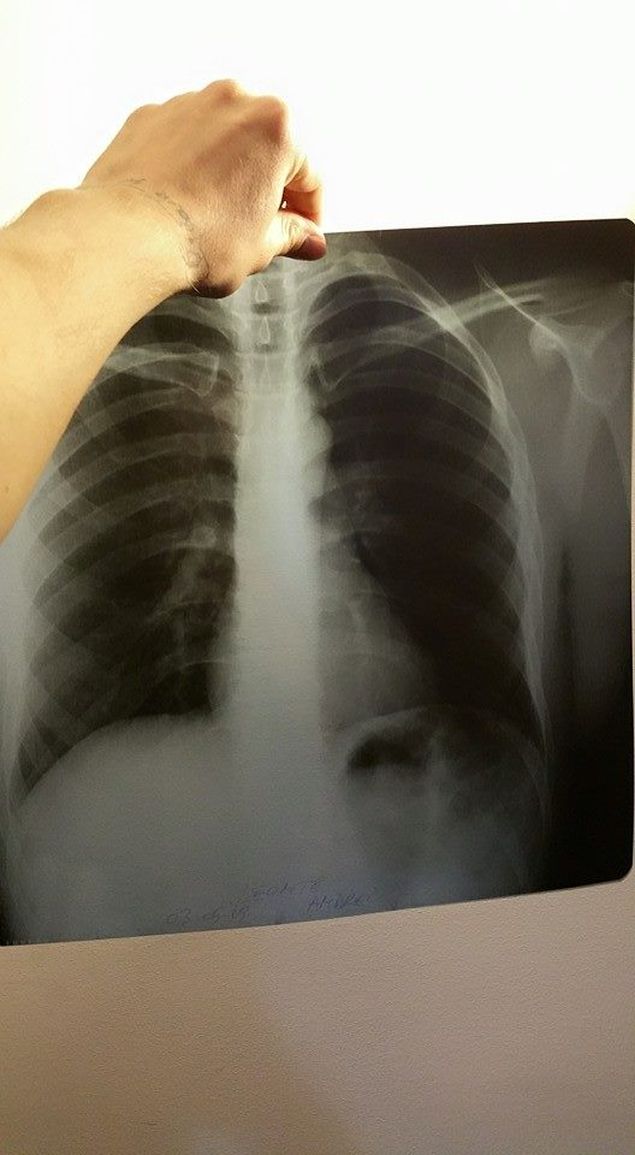

"A început cu o durere de spate, care nu sunt străine, eu am scolioză, a fost ceva mai puternic, am luat nişte pastile la recomandarea farmacistei, m-am luat cu stare de leşin, asta ieri de dimineaţa. A venit ambulanţa, am mers la spital. S-a combinat cu o radiografie prost făcută, arăta ceva ce nu era adevărat, asta i-a indus în eroare.